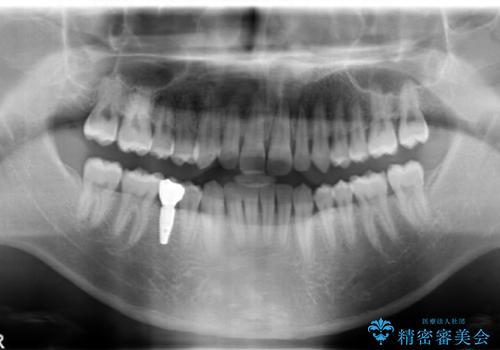

矯正治療終了後のインプラント植立については以下をご覧ください。

https://seimitsushinbi.jp/case/63803/

右下に乳歯が残っていましたが、後に続く永久歯がありませんでした。

乳歯も根が吸収しており長くは持たない状況でしたので、まず乳歯を抜歯し、他の歯を矯正治療で歯を並べてからインプラントで補綴しました。

先にインプラントをしてしまうと、矯正治療で周りの歯を動かす事ができなくなってしまいます。

矯正治療→インプラントの順で行います。